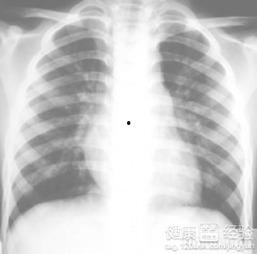

这个视频一开始就让人眼前一亮,因为它采用了动画的形式,将支气管肺炎的发病过程生动地呈现在我们面前。你可以看到,视频中的人物从正常呼吸到出现咳嗽、呼吸困难,再到肺部出现炎症,整个过程都被形象地描绘出来。这种直观的展示方式,让我们对支气管肺炎有了更深刻的认识。

支气管肺炎的症状有很多,视频中也一一列举。比如,患者会出现咳嗽、咳痰、呼吸困难、发热、乏力等症状。这些症状可能会持续一段时间,严重时甚至会影响日常生活。视频中的动画演示,让我们对这些症状有了更直观的感受。